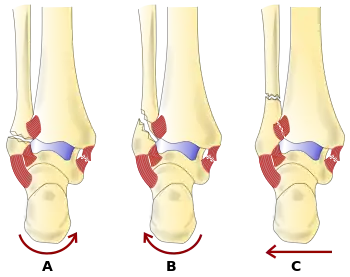

Danis–Weber classification of ankle fractures (Types A, B and C)

Fracture of the fibula distal to the syndesmosis (the connection between the distal ends of the tibia and fibula). Typical features:

• below level of the ankle joint

• tibiofibular syndesmosis intact

• deltoid ligament intact

• medial malleolus occasionally fractured

• usually stable: occasionally nonetheless requires an open reduction and internal fixation (ORIF) particularly if medial malleolus fractured

Fracture of the fibula at the level of the syndesmosis. Typical features:

• at the level of the ankle joint, extending superiorly and laterally up the fibula

• tibiofibular syndesmosis intact or only partially torn, but no widening of the distal tibiofibular articulation

• medial malleolus may be fractured or deltoid ligament may be torn

• variable stability

Fracture of the fibula proximal to the syndesmosis. Typical features:

• above the level of the ankle joint

• tibiofibular syndesmosis disrupted with widening of the distal tibiofibular articulation

• medial malleolus fracture or deltoid ligament injury present

• unstable: requires ORIF

Categories B and C imply a degree of damage to the syndesmosis itself (which cannot be directly visualised on X-ray). They are inherently unstable and are more likely to require operative repair to achieve a good outcome. Type A fractures are usually stable and can be managed with simple measures, such as a plaster of paris cast.